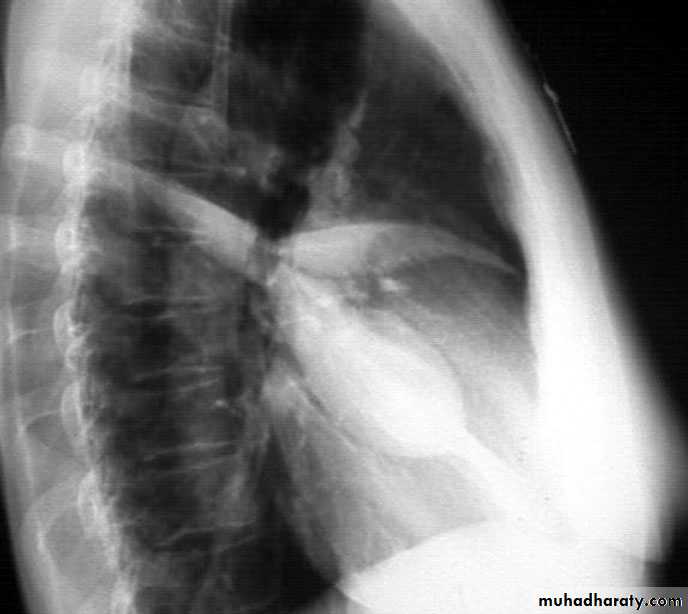

Upper lobe c. Middle lobe c.

rt lower lobe c. Left lower lobe c.

Left upper lobe collapse